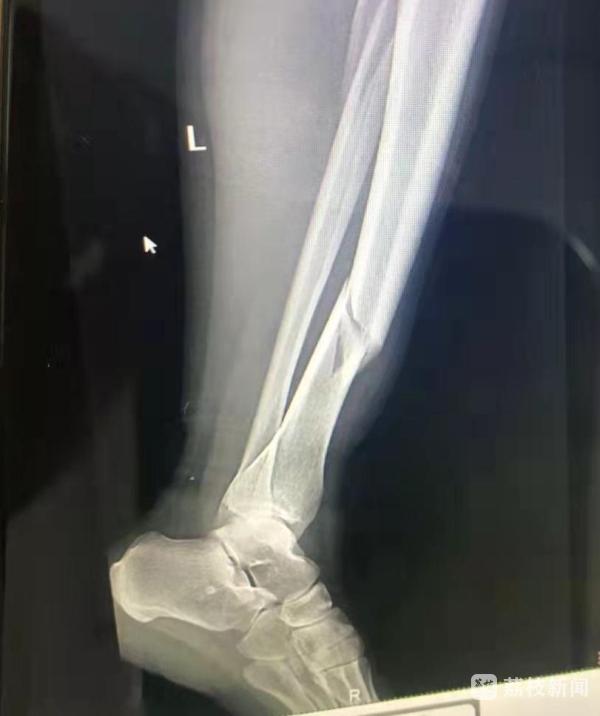

旁边的人看到玲玲的样子都忍不住大笑起来,可过了好一会,大家发现玲玲还没站起来,甚至疼得连话都说不出来,于是赶紧拨打了 120,玲玲被直接被送进了连云港市第一人民医院急诊室。片子一拍,傻眼了,还没见到滑雪场啥样,玲玲的腿骨折了。目前,玲玲手术完正在住院接受进一步治疗。

滑雪受伤以下肢占比最高,其中膝、踝关节及小腿受伤多见。受伤类型中又以韧带的损伤和骨折最为常见。滑雪运动避免受伤,应注意以下 5 点: